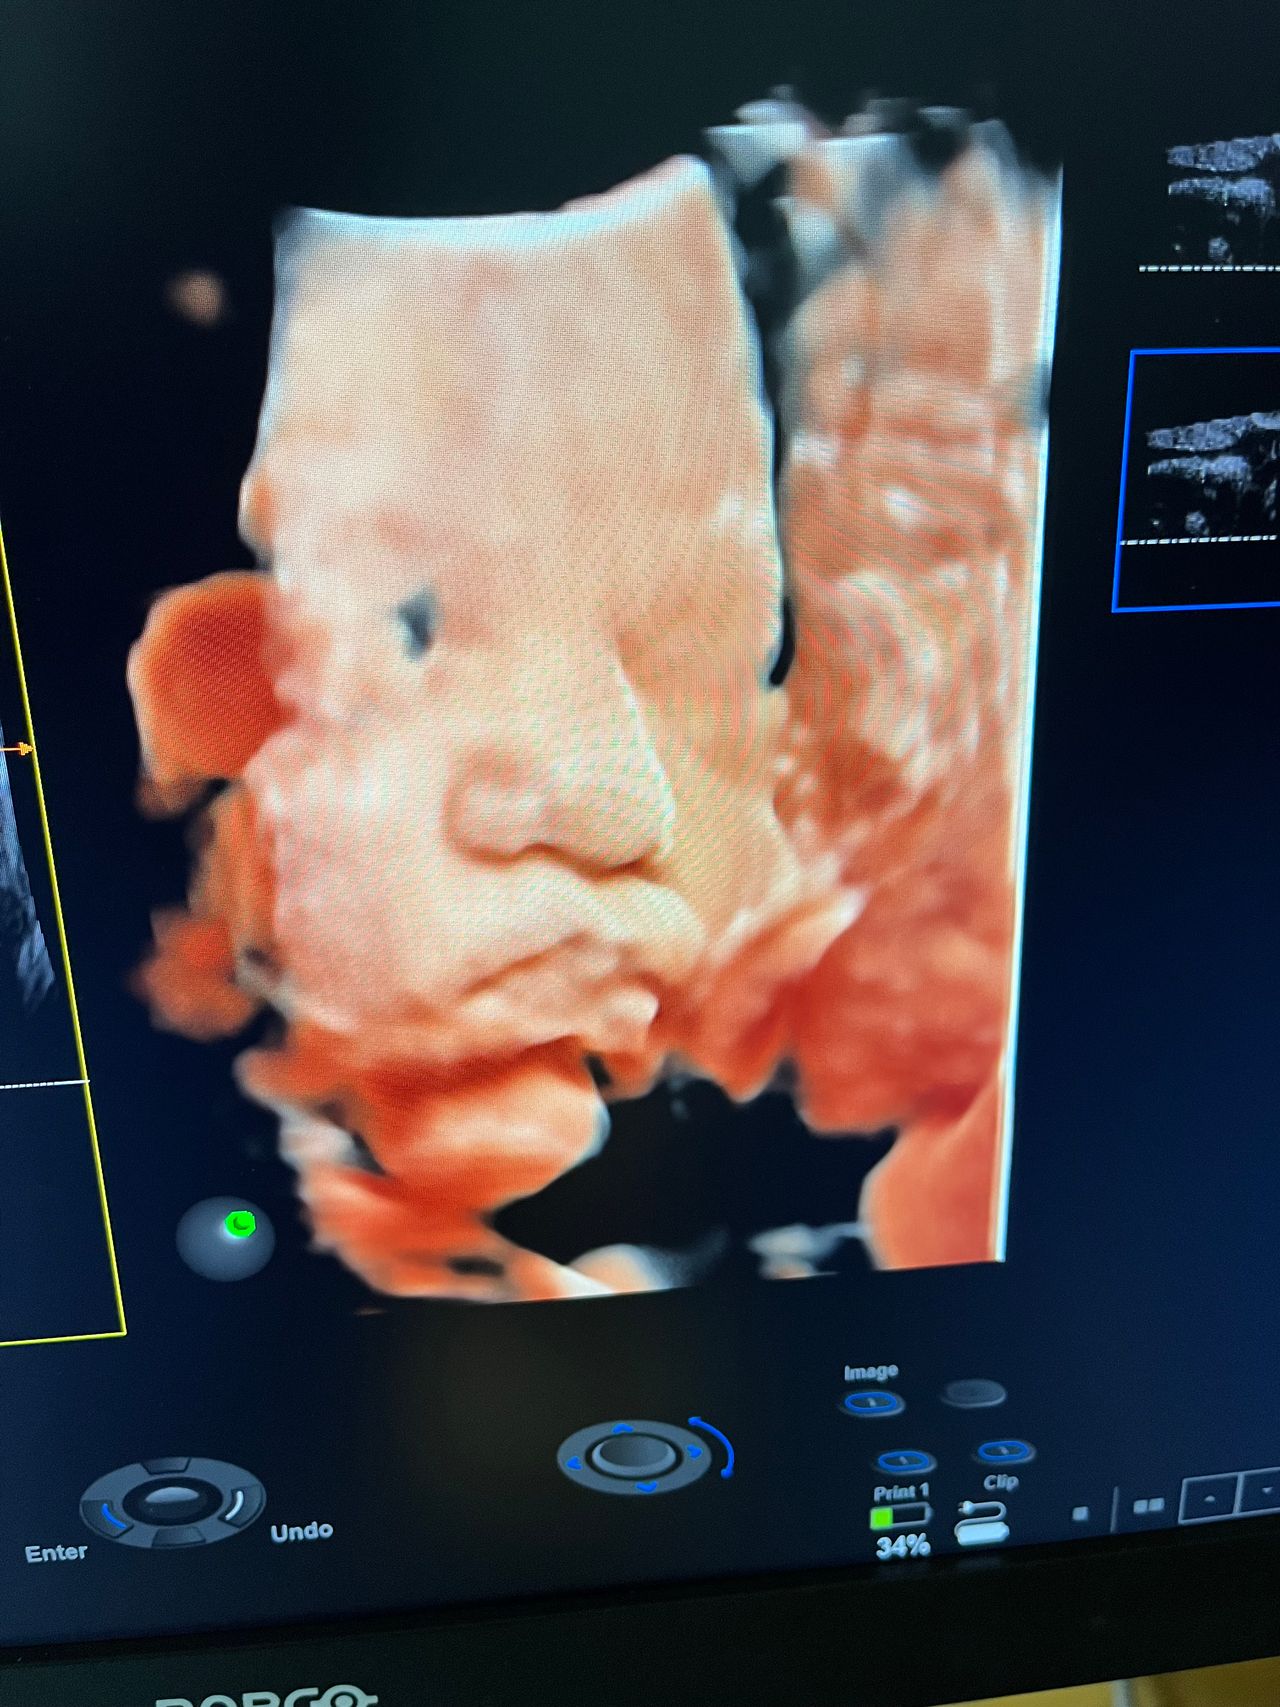

Attualmente lavoro come Dirigente medico nella SC di Ostetricia e Ginecologia dell'Ospedale Michele e Pietro Ferrero di Verduno, mi occupo prevalentemente di screening prenatale, ecografia ostetrica del I trimestre( misurazione translucenza nucale,NT), ecografia morfologica del II trimestre, ambulatorio pregresso taglio cesareo, ecografia ostetrica 3D. Seguo le gravidanze fisiologiche e quelle ad alto rischio , presto servizio in sala parto. Eseguo visite ginecologiche di I-II livello in regime ambulatoriale, counseling contraccettivo ed eventuale prescrizione pillola, inserimento spirale (IUD), dispositivo sottocutaneo (Nexplanon).

Foto e video